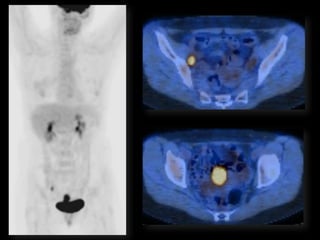

Dr. Hedvig Hricak

HISTORY

•   42 yo female

•   Recent immigrant from China

•   C/O postcoital and intermenstrual bleeding

•   Abnormal GYN exam

•   Abnormal biopsy

•   Further imaging performed

• What is the diagnosis?

• Staging?